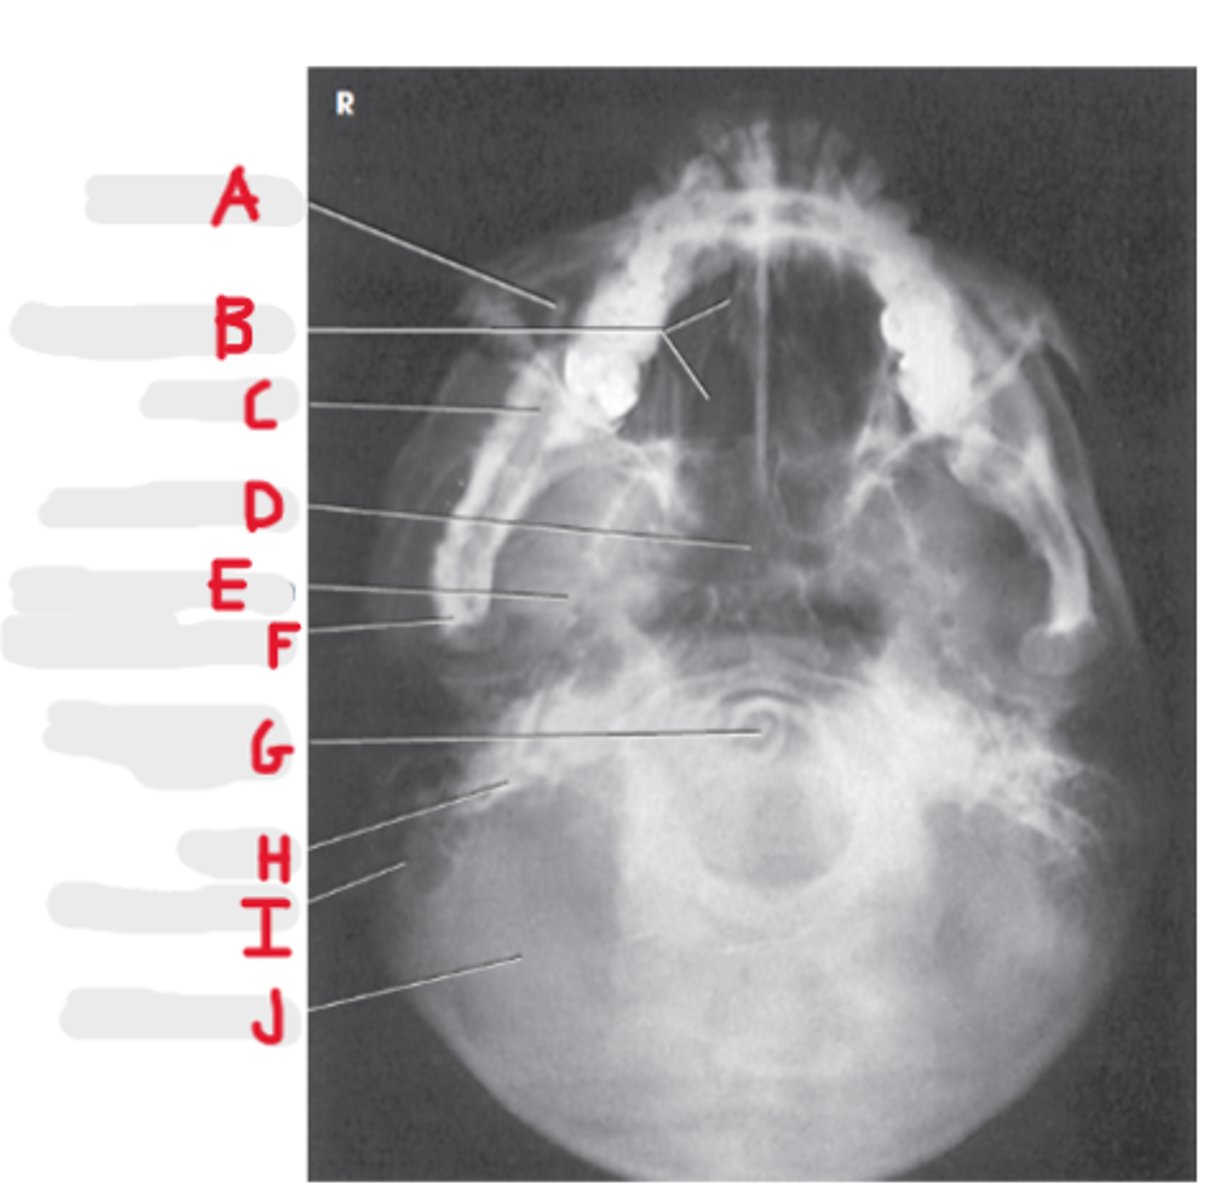

Maxillary sinus

A

Ethmoid air cells

B

Mandible

C

Sphenoid Sinus

D

Foramen spinosum

E

Mandibular condyle

F

Dens or odontoid process

G

Petrosa

H

Mastoid process

I

Occipital bone

J

Submentovertex (or vertical) SMV

What projection is this?

CR - perpendicular to IOML

enters 1-1 1/2 inch below the mentum

What is the CR for the SMV?

Infraorbital meatal line (IOML)

What line is parallel to the IR for the SMV?

Basal view because it demonstrates the base of the skull

What is the SMV known as and why?

Sphenoid and ethmoid

What sinuses are best demonstrated on an SMV?

Look for equidistant lateral border of skull to mandibular condyles

How do we look for rotation/tilt on an SMV radiograph?